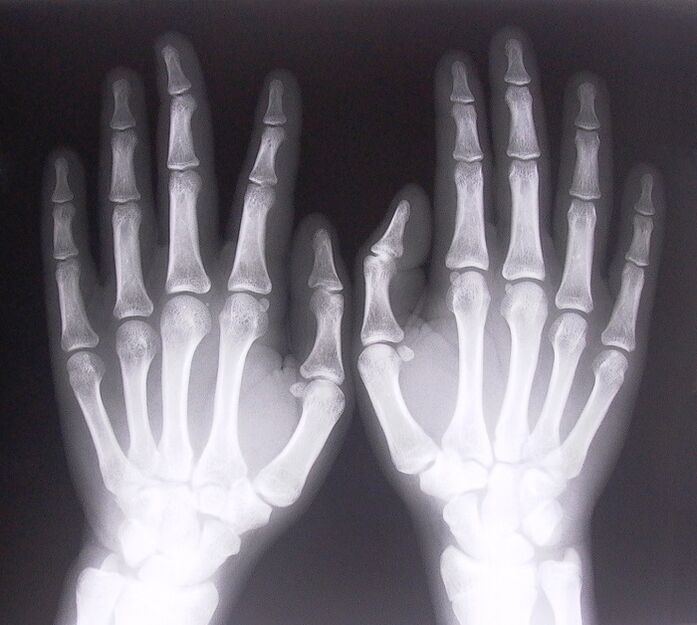

- Stenotic ligamentitis.To identify the cause of the disease, it is necessary to undergo an X-ray.The symptoms are typical: painful movement of the hand, bending of the clenched palm.Also, during extension, clicks are usually heard.

To start treating joint pain in the fingers, you need to determine exactly what disease caused them.To determine what kind of disease is affecting a person who feels pain in the joints when bending the arms, doctors recommend undergoing the following procedures:

- Take x-rays.